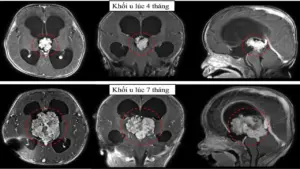

TPHCM: Cấp cứu cháu bé có khối u não to gấp ba lần chỉ trong 3 tháng

Ngày 8/4, đại diện Bệnh viện Nhi đồng 1 (TPHCM) cho biết, vừa qua các [...]